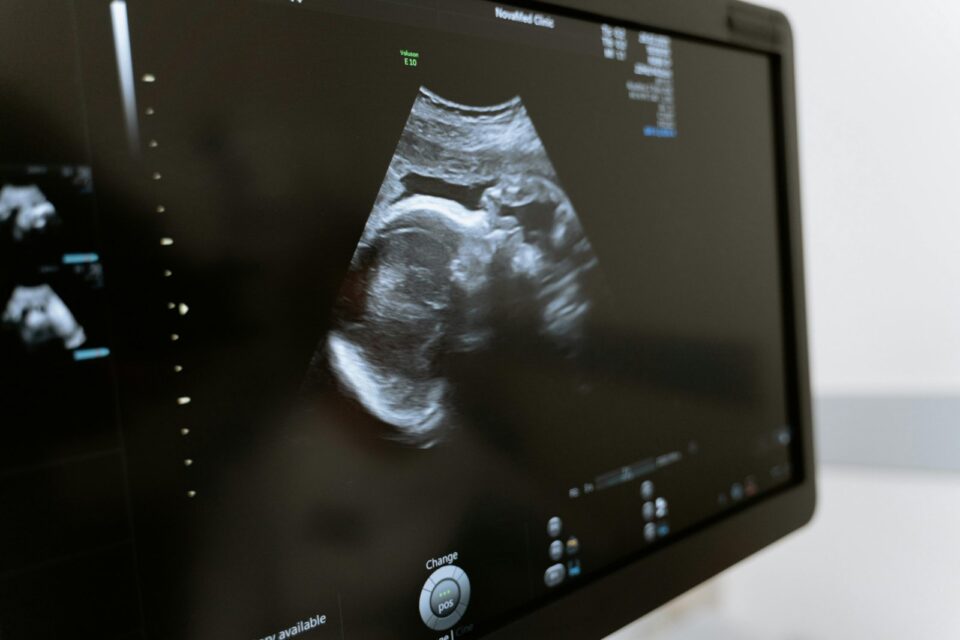

Κατόπιν αυτού, με την υποστήριξη και της οικογένειάς της, η 34χρονη γυναίκα αποφάσισε να προχωρήσει στο επόμενο βήμα, επιδιώκοντας μια εγκυμοσύνη με μεταφορά των ήδη κρυοσυντηρημένων γονιμοποιημένων ωαρίων. Η εξωσωματική γονιμοποίηση που ακολούθησε ήταν επιτυχής και η κύηση είναι πλέον σε εξέλιξη.